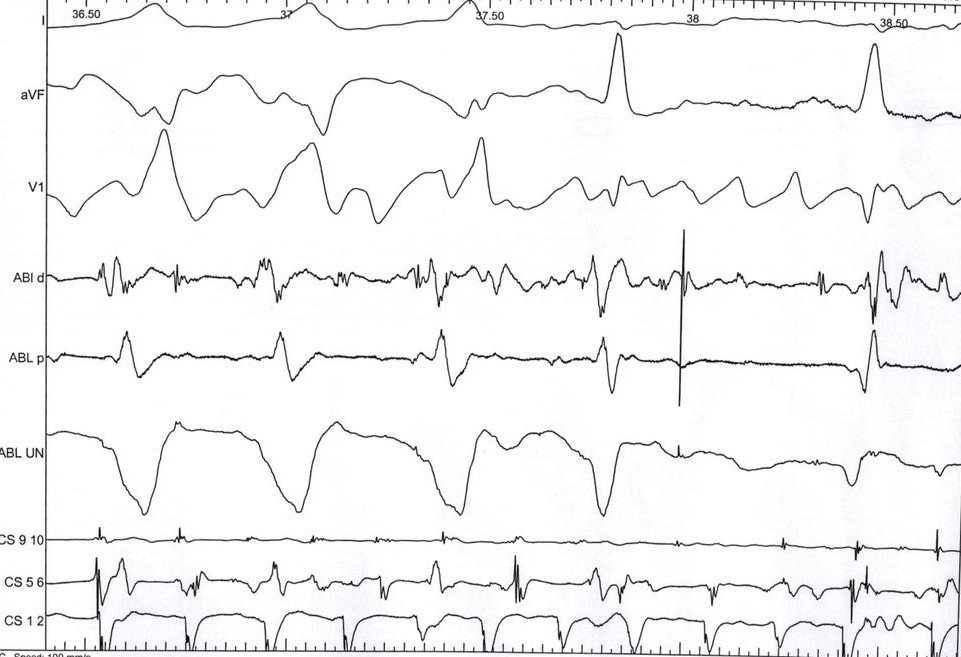

Ablation page

abl_page.jpg